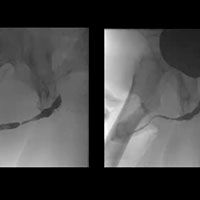

Posterior Urethroplasty for Pelvic Fracture Urethral Injury video image

Posterior Urethroplasty for Pelvic Fracture Urethral Injury

Dr. Jeremy Myers, from University of Utah, demonstrates posterior urethroplasty for treatment of urethral injury after a pelvic fracture.

Dr. Jeremy Myers, from University of Utah shows posterior urethroplasty for repair of urethral injury after pelvic fracture.